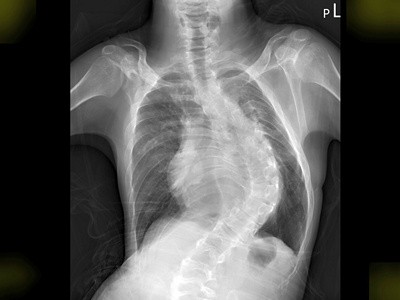

圖:病人徐先生置放心律調節器前(左圖)、後(右圖)的X光檢查圖。

但是徐先生患有先天性罕見疾病畢耳氏症候群(Beals Syndrome),是一種結締組織異常的遺傳性疾病,導致生長發育遲緩,並伴隨心血管方面的併發症。徐先生雖然已經23歲,卻只有25公斤、132公分高的身形,加上嚴重的胸部脊椎側彎、胸腔窄小、心臟偏右側、加上心臟血管走向異常,患有發生率僅0.3%的「持續性左上腔靜脈」,也就是比一般人,多了一條胚胎期未退化的左上腔靜脈,大幅增加手術的困難度。

徐先生日前因心跳異常緩慢,每分鐘只有二十至三十下,稍微一動就會「很喘」,由心臟內科張懷仁醫師收治,確診為「完全性房室傳導阻斷」,並建議置放心律調節器。但因徐先生有嚴重胸部脊椎側彎、心臟偏右側、加上心臟血管異常,且患有發生率僅0.3%的「持續性左上腔靜脈」,大幅增加手術的困難度。經過一個月的沙盤推演,張懷仁醫師與醫療團隊於四月中旬成功為徐先生置放心律調節器。徐先生術後復原良好,短短一星期的住院期間,更增胖了2公斤。